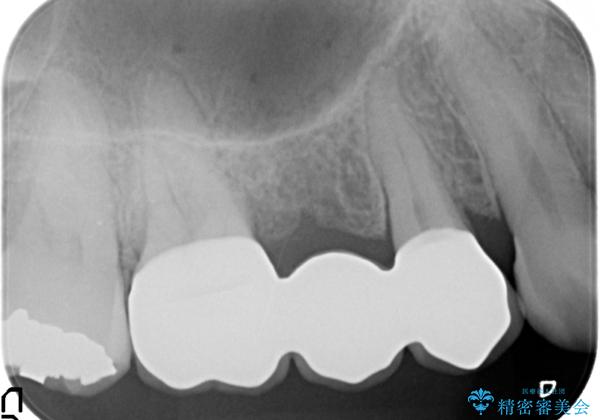

虫歯による歯の崩壊で歯を残すことが難しかったので抜歯を行い、インプラント・入れ歯ではなくブリッジによる咬合機能の回復を希望されました。

- 33万円(仮歯・ジルコニアクラウン×3)費用は治療当時の料金となります

ブリッジは隣の歯を削り、クラウンにしなければならないというデメリットはありますがインプラントと異なり手術をしなくてもよく、入れ歯よりも一般的にしっかりと噛むことができます。